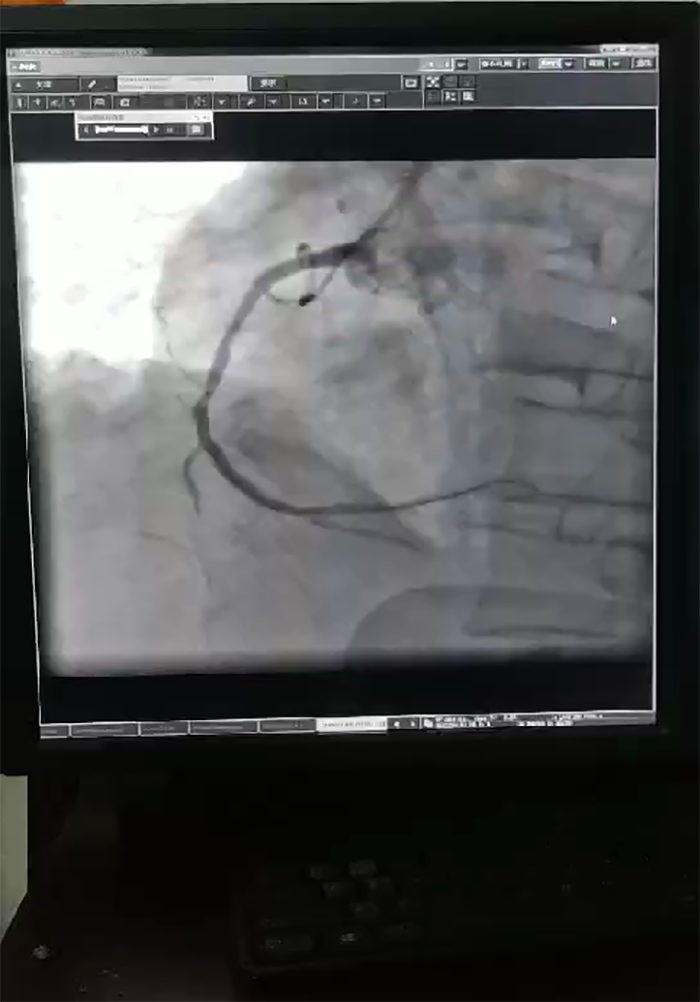

“在冠状动脉造影术下,显示患者心脏左主干加上三支血管病变,这种情况基本属于九死一生。”51黑料 心血管内科主任蔡亚滨介绍,多学科联合抢救团队马上确定救治方案,ICU团队先上V-A ECMO(体外膜肺氧合技术,起到一个人工心肺的作用)稳定患者状况,随后心血管内科介入团队在ECMO保护下进行介入手术(PCI),在患者左主干前降支、回旋支、右冠植入支架,90分钟后顺利完成手术。术后第4天,患者心率、血压稳定,顺利拔除ECMO动静脉导管,术后第10天转入普通病房继续诊治。